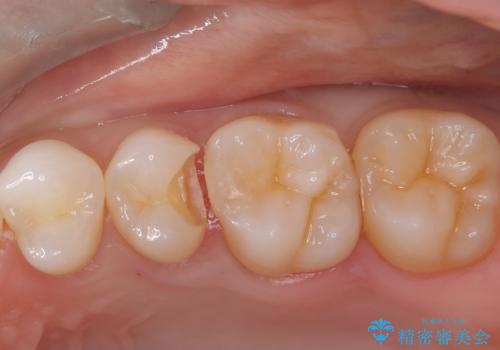

- クリーニング時に治療が必要な大きさの虫歯が見つかりました。

審美性と材料の安定性からセラミックでの修復を行うこととなりました。

う蝕を除去し、CRにて裏層をし、セラミックインレーにて修復しました。

ラバーダム防湿をした上で、接着しました。